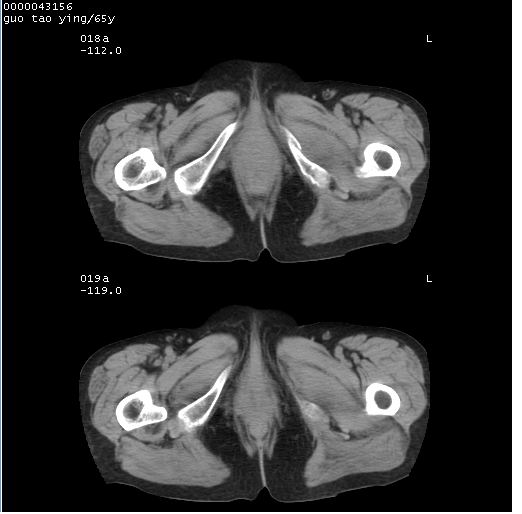

以下是引用黑白光影在2008-1-30 13:22:00的发言:[br]支持左耻骨骨折。[br]未见骶骨骨质明确破坏改变。[br]经楼主提示(勿局限于外伤)。考虑为右侧腹股沟直疝。[br][br][br][br]